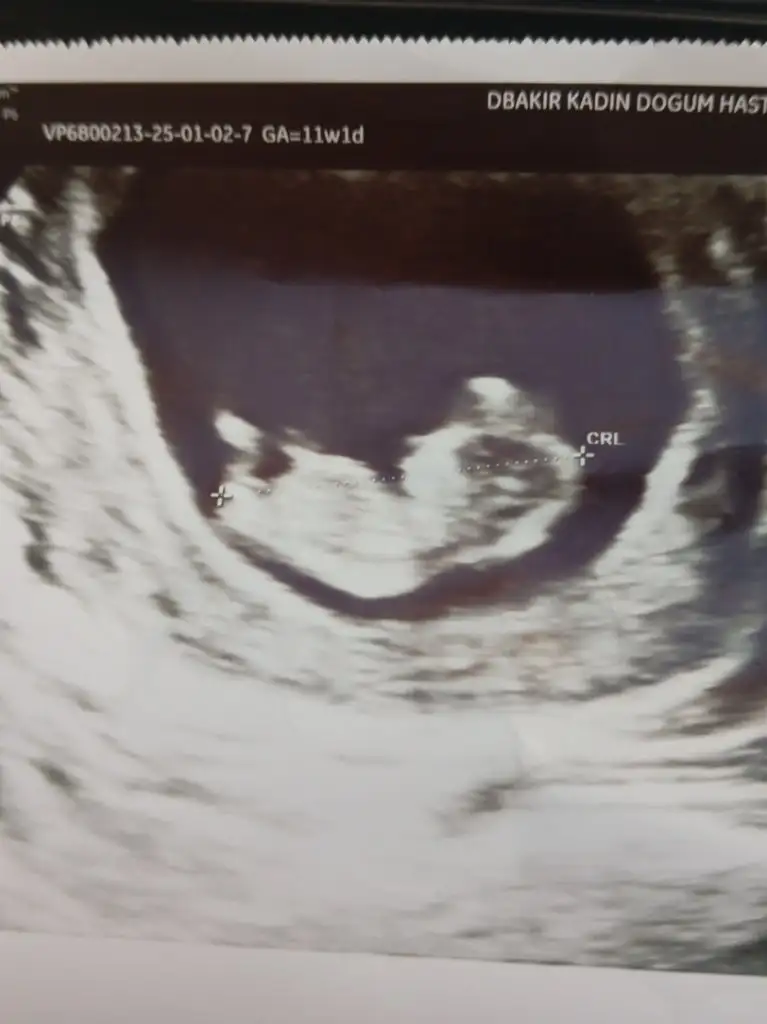

Anlıyorsaniz benimkine de bakarmisiniz aceba rica edersem 11 ve 9 haftalık

• 1000926651.webp

1000926651.webp

18,2 KB · Görüntüleme: 93

• 1000924618.webp

1000924618.webp

20,4 KB · Görüntüleme: 87